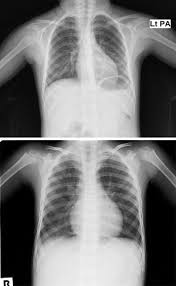

- 흉부 X-ray: 기관지 주위 침윤, 폐렴 소견